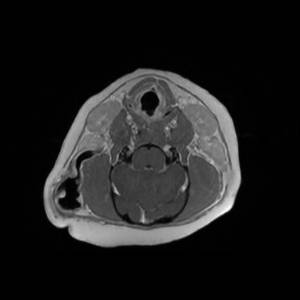

Main Gallery

Playing with a photo gallery function. It is possible to have multiple galleries, each within a namespace.